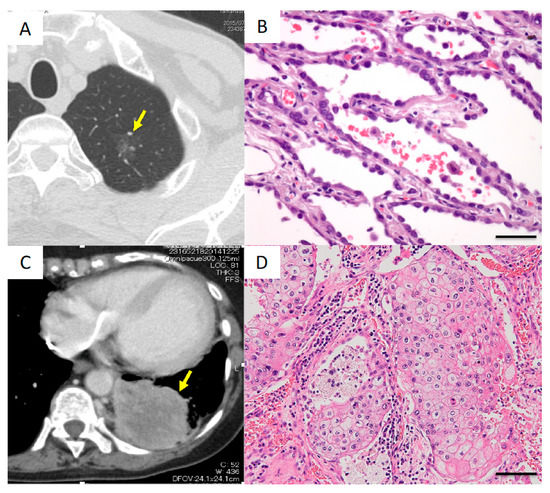

Case I

Case II

Case III